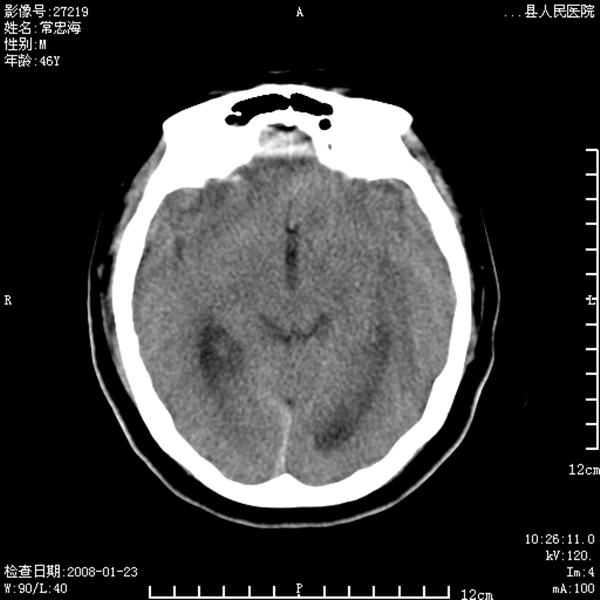

以下是引用江边学者在2008-4-19 22:26:00的发言:[br]1.胼胝体发育不良。[br]2.右侧眼球痨。[br]3.右侧颜面部软组织挫伤。